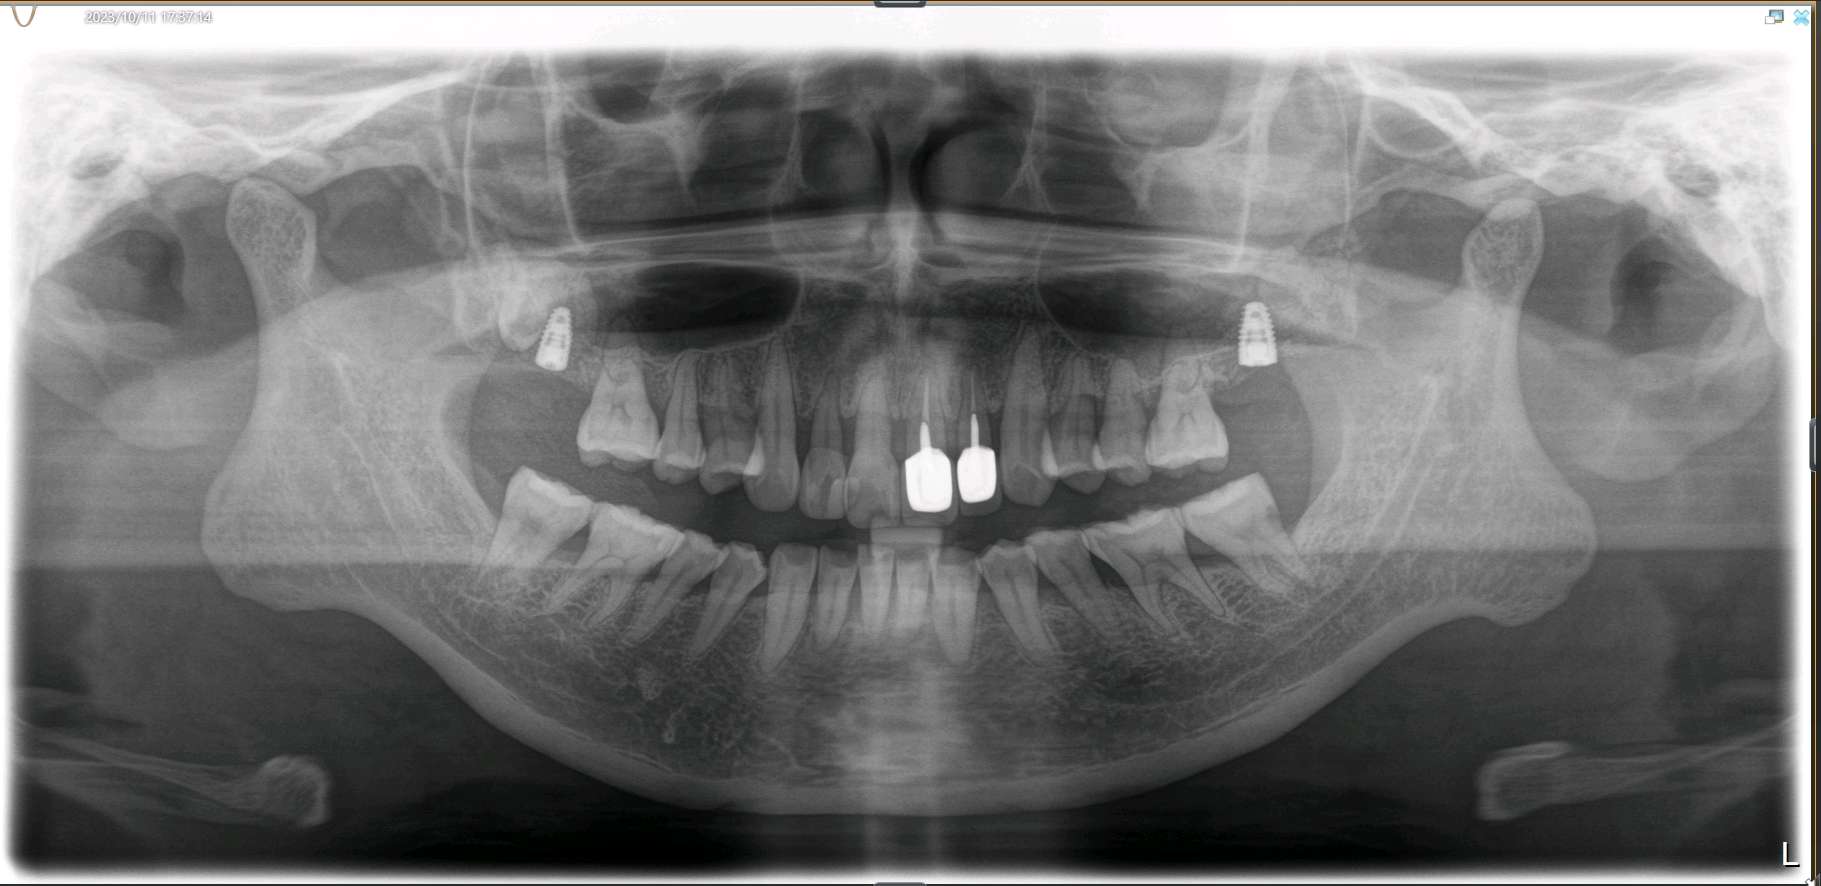

患者女,45岁。患者自述有刷牙出血症状,探易出血,探及牙周袋深度5mm,可探及袋内牙石3mm。21、22已行根管治疗加桩冠修复,牙龈萎缩,边缘不密合,21牙颈部楔缺。中切牙之间缝隙较大。12邻面部分充填物。。X线示根尖无阴影。患者自觉前牙不美观,要求重新修复。

治疗计划:1、牙周治疗。2、21,22饵激光拆除牙冠。清理基牙,重新预备,西诺德全冠修复。3、11、12贴面修复。